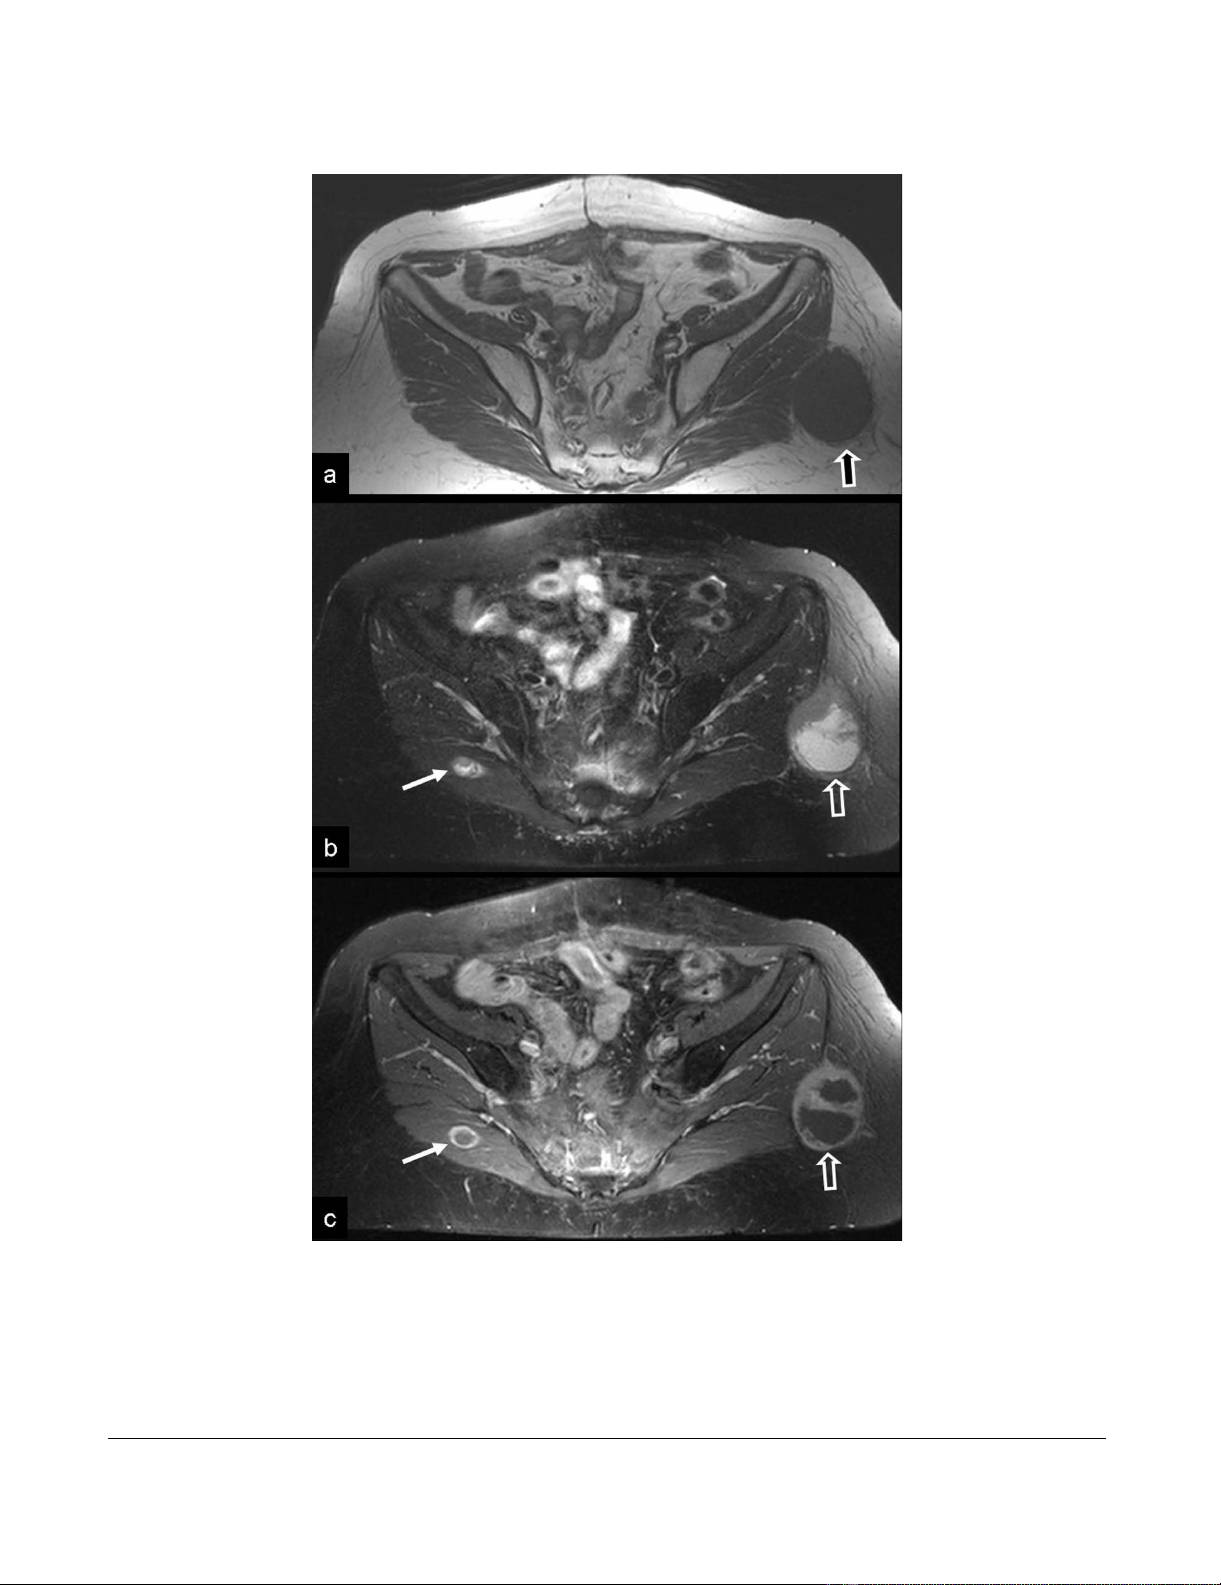

Metastatic disease from extragastrointestinal GISTFigure 3

Metastatic disease from extragastrointestinal GIST. a) The axial T1-w MR image shows an intermediate signal intensity

ovoid-shaped mass, lateral to the gluteus maximus muscle, within the subcutaneous fat (arrow). An intact fat plane separated

the mass from the muscle. b) The fat suppressed T2-w TSE MR image, shows the high signal intensity of the central mass and

the intermediate signal intensity of the anterior wall (open arrow). A second smaller lesion with similar imaging characteristics

is shown in the right gluteus maximus muscle (thin arrow). c) The contrast enhanced fat suppressed T1-w SE MR image shows

the peripheral enhancement of the wall (open arrow). The central non enhancing component presumably corresponds to

necrosis. Ring-like enhancement is also shown in the smaller lesion (thin arrow).